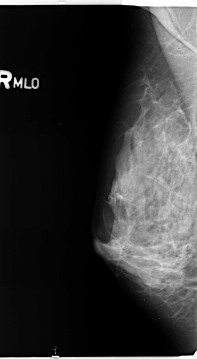

B_3359_1.RIGHT_MLO

RIGHT_CC LINES 4736 PIXELS_PER_LINE 2736 BITS_PER_PIXEL 12 RESOLUTION 50 NON_OVERLAY

RIGHT_MLO LINES 4664 PIXELS_PER_LINE 2552 BITS_PER_PIXEL 12 RESOLUTION 50 NON_OVERLAY